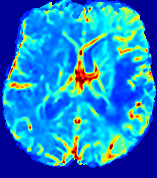

LesionRefer to captionRefer to captionRefer to captionRefer to captionRefer to captionRefer to caption𝐕rgbsubscript𝐕𝑟𝑔𝑏{\bf{V}}_{rgb}Refer to captionRefer to captionRefer to captionRefer to captionRefer to captionRefer to caption𝐕2subscriptnorm𝐕2{\|\bf{V}}\|_{2}Refer to captionRefer to captionRefer to captionRefer to captionRefer to captionRefer to captionRefer to caption3.53.53.52.82.82.82.12.12.11.41.41.40.70.70.70.00.00.0(mm/s)𝑚𝑚𝑠(mm/s)D𝐷DRefer to captionRefer to captionRefer to captionRefer to captionRefer to captionRefer to captionRefer to caption0.0200.0200.0200.0160.0160.0160.0120.0120.0120.0080.0080.0080.0040.0040.0040.0000.0000.000(mm2/s)𝑚superscript𝑚2𝑠(mm^{2}/s)Slice #1Slice #2Slice #3Slice #4Slice #5Slice #6

Figure 3: PIANO feature maps for one stroke patient, where the lesion is located in the left hemisphere. Top row: segmented stroke lesion region (white) on different slices, obtained from ISLES 2017. The corresponding slices for the PIANO feature maps are shown in the following rows.

For a better insight into an estimated velocity field 𝐕𝐕{\bf{V}} and diffusion field 𝐃𝐃{\bf{D}}, we compute the following maps: (1) 𝐕rgbsubscript𝐕𝑟𝑔𝑏{\bf{V}}_{rgb}: Color-coded orientation map of 𝐕=(Vx,Vy,Vz)T𝐕superscriptsuperscript𝑉𝑥superscript𝑉𝑦superscript𝑉𝑧𝑇{\bf{V}}=(V^{x},V^{y},V^{z})^{T}, obtained by normalizing 𝐕𝐕{\bf{V}} to unit length and mapping its 3 components to red, green, blue respectively; (2) 𝐕2subscriptnorm𝐕2\|{\bf{V}}\|_{2}: 222 norm of 𝐕𝐕{\bf{V}}; (3) D𝐷D: scalar field in Eq. 5.

Fig. 3 and Fig. 4 show the PIANO feature maps estimated from two ISLES 2017 patients: all are highly consistent with the lesion in both cases. Details of the blood flow trajectories are revealed in 𝐕rgbsubscript𝐕𝑟𝑔𝑏{\bf{V}}_{rgb} by the ridged patterns and the sharp changes of colors in the unaffected (right) hemisphere, while the flat patterns appearing within the lesion provide little directional information about the velocity and indicate low velocity magnitudes. Velocity magnitudes are more directly visualized via 𝐕2subscriptnorm𝐕2\|{\bf{V}}\|_{2}, from which one can easily locate the lesion where 𝐕2subscriptnorm𝐕2\|{\bf{V}}\|_{2} is low. D𝐷D also indicates lower diffusion values in the lesion, though with less contrast potentially due to the fact that it captures the accumulated effect of CA diffusion at the voxel-level.